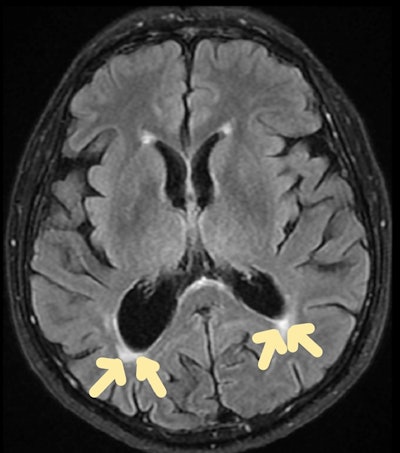

Organophosphate poisoning. Axial MRI scan shows fluid-attenuated inversion recovery (FLAIR) hyperintensity in caudate and lentiform nucleus of brain.

In these cases, CT shows hypoattenuation bilaterally in the basal ganglia. MRI shows diffusion restriction with symmetrical T2 or T2 fluid-attenuated inversion recovery hyperintensities involving bilateral globus pallidus with extension to the posterior limb of bilateral internal capsules and bilateral cerebellar hemispheres, which indicates acute infarcts.